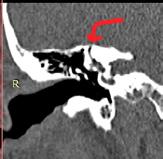

Examenul CT cu rezoluție înaltă poate evidenția dehiscența de la nivelul canalului semicircular superior. Interpretarea trebuie făcută cu prudență pentru că uneori, dacă osul care acoperă canalul este foarte subțire pot exista rezultate fals pozitive. Pentru o mai bună acuratețe se folosesc secțiuni fine sub 0.5 mm și reconstrucții în planul canalului (Pöschl) sau octogonal față de acesta (Stenvers). Examenul prin rezonanță magnetică (RMN) poate completa informațiile obținute la CT, poate exclude prezența unei fistule în cazul osului subțire. Este foarte utilă de asemenea în eliminarea unei patologii cerebrale (5) .

2b

Fig. 2 Pacientă internată în Clinica ORL SCJU Cluj-Napoca cu simptome sugestive pentru SCD la urechea dreaptă. Examinare CT-se observă breşa la nivelul CSS în incidență sagitală (a) şi în planul CSS (b). Potențiale evocate vestibulare miogene